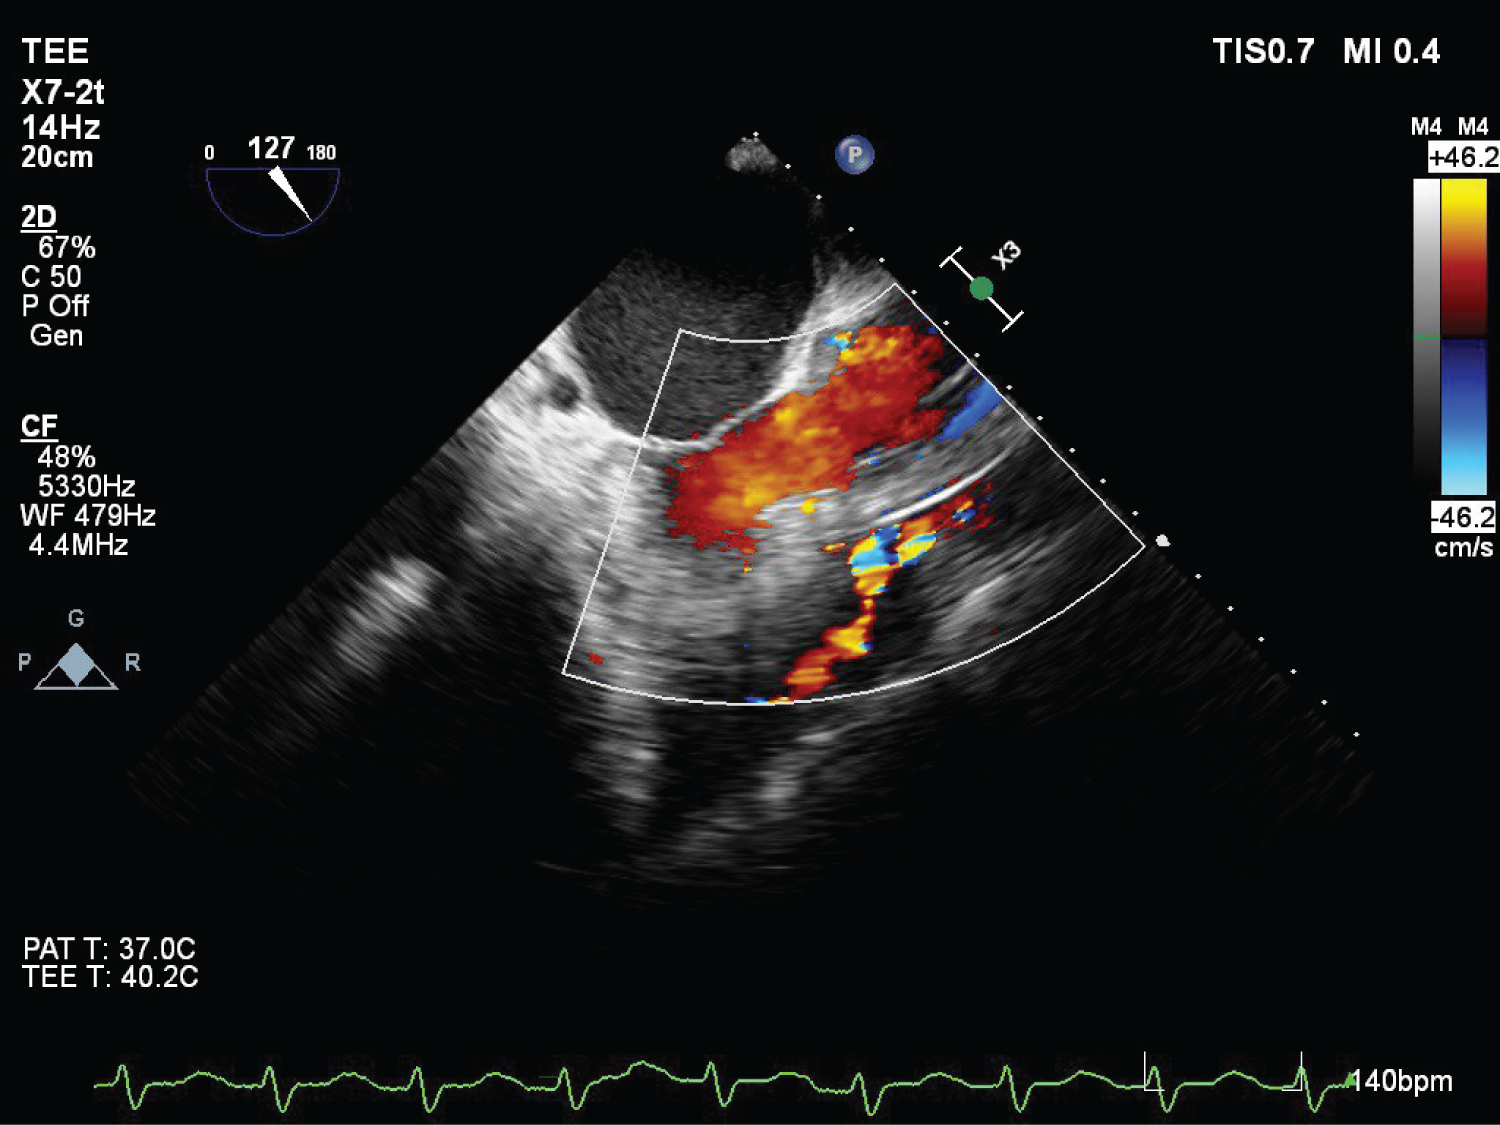

On echocardiography, aneurysmal appearance of the involved sinus and the presence of a “windsock,” protruding into the receiving chamber are characteristic of RSOV [7] (Figure 1, Figure 2, Figure 3, Figure 4 and Figure 5) ( Video 1 and Video 2 ).

Figure 2: (TEE) Mid esophageal RV inflow-outflow view with colour doppler showing RSOV, VSD hypertrophied RV ridge. View Figure 2

Figure 3: (TEE) Mid esophageal four chamber view with colour Doppler showing blood flow across VSD (Left to right shunt). View Figure 3